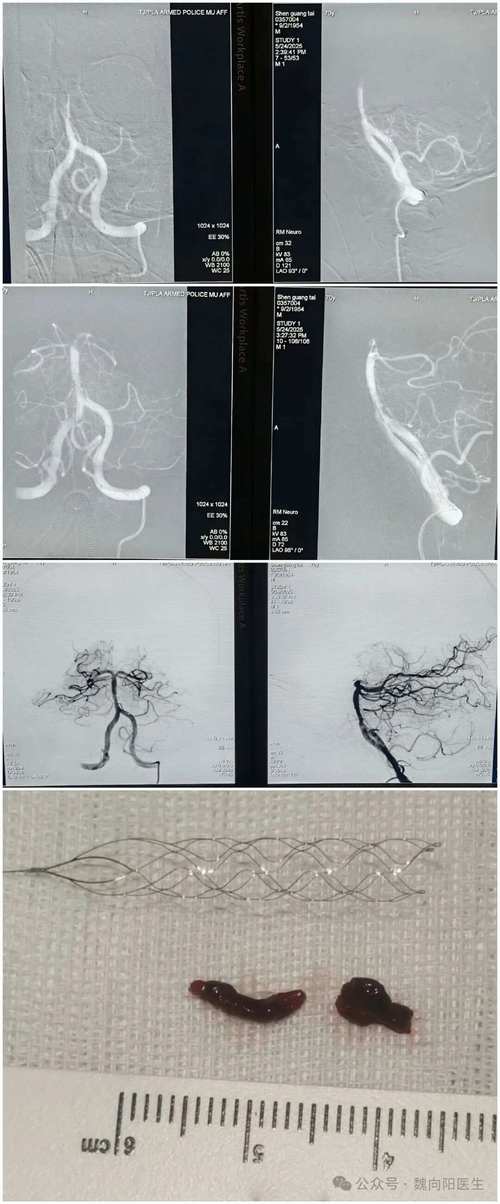

- 动脉取栓:这是目前治疗大血管闭塞(如基底动脉)的最有效方法,医生通过介入手术,从大腿根部的血管放入导管,一路送到脑血管的堵塞处,用支架或取栓器将血栓直接取出。时间窗相对宽一些(可达24小时,但越早越好),对于昏迷的病人,只要影像学评估显示脑组织还有挽救的可能,都会积极尝试。